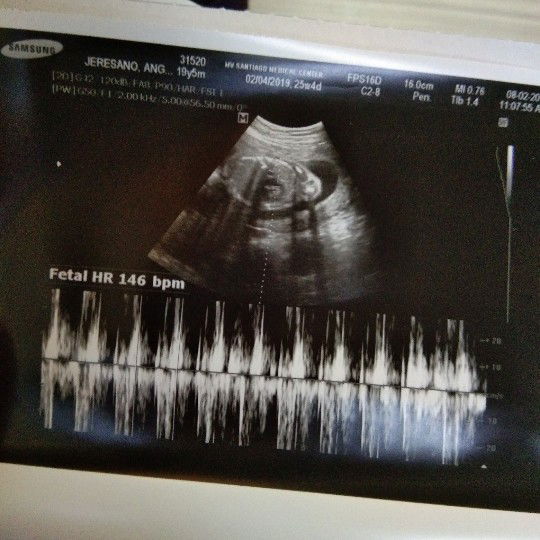

Proud Soon to be mom! ❤

Mga mommy share ko lang tong experience ko sa pagbubuntis ko. 25 weeks na po ako at EDD ko is sa November 15. BABY BOY PO HEHE! first time mom. Feb 4 ang last means ko and march di na ko dinatnan pero di ko expected na buntis na ako kase irregular means ako at kahit anong sintomas ng pagbubuntis wala akong naramdaman, ni pagcrave sa mga pagkain wala, ni suka or yung morning sickness na nararanasan hanggang ngayon is wala hindi ko naexperience yun. Simula march na hindi na ako nagkaroon hanggang nung july 30 hindi talaga ako nagpacheck up kase baka delay lang talaga ako pero lumalaki na tyan ko kaya nagdecide kami ng boyfriend ko na magpacheck up na kase lumalaki na tyan ko at yung parang may nagalaw sa tiyan ko. Kaya nung July 31 nagpacheck up na po ako at nasched ako na magpautz kanina lang through pelvic at ayun nga confirm preggy nga ako 25 weeks at healthy pa at normal lahat kahit na wala pa kami iniinom na vitamins noon dahil late ko na talaga nalaman. Thank you talaga kay Lord kase hindi nya pinabayaan baby ko sa tummy ko even late ko na nalaman. Yung hindi mo sya expected mga mommshie! ? Kase hindi nya talaga ako pinapahirapan magbuntis ni baby ngayon at sana hindi nya rin ako pahirapan manganak hehe! ? Kaya tiwala lang mga momsh! Ito talaga di ko expected pero dumating saken tong pinakamagandang blessing samin ! ?❤ Ito na sya oh! ??? 25 WEEKS AND 4 DAYS! BABY BOOOY!? Edd. November 15 ❤ Thanks G. Ang sarap sa feeling ❣️